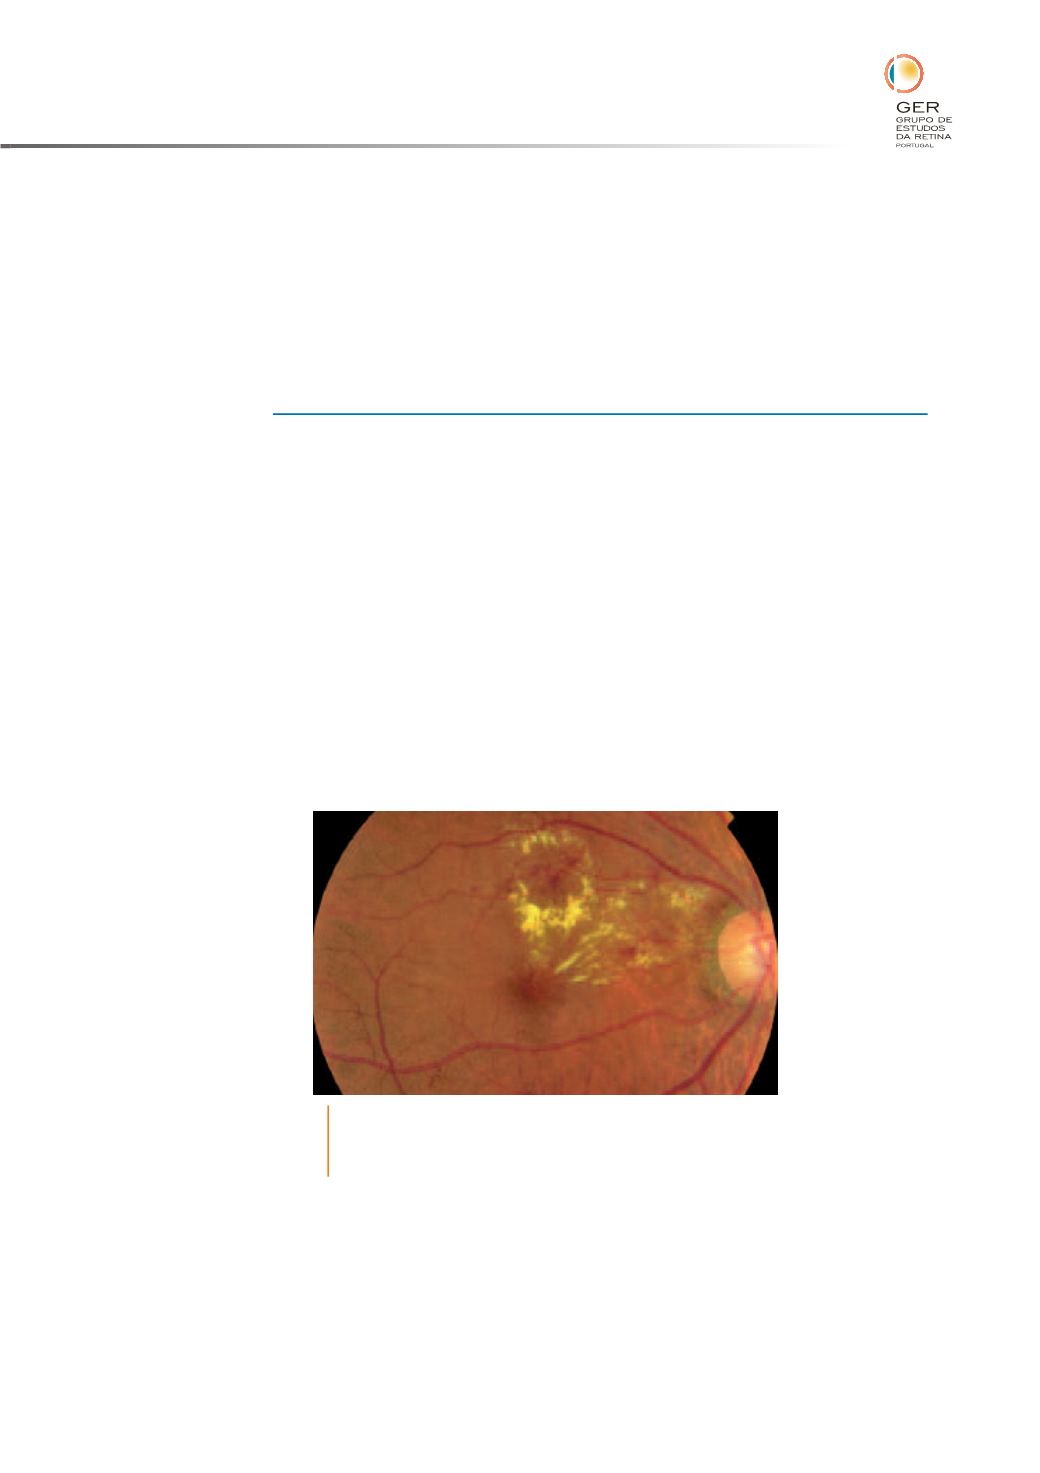

. O edema focal (%gura

1) é causado por difusão focal a partir dos microaneurismas e é de%nido como

um agregado de microaneurismas rodeados por anel circinado de exsudados

Fig. 1

O EMD focal é de%nido como um agregado de

microaneurismas rodeados por anel circinado de exsudados

duros.